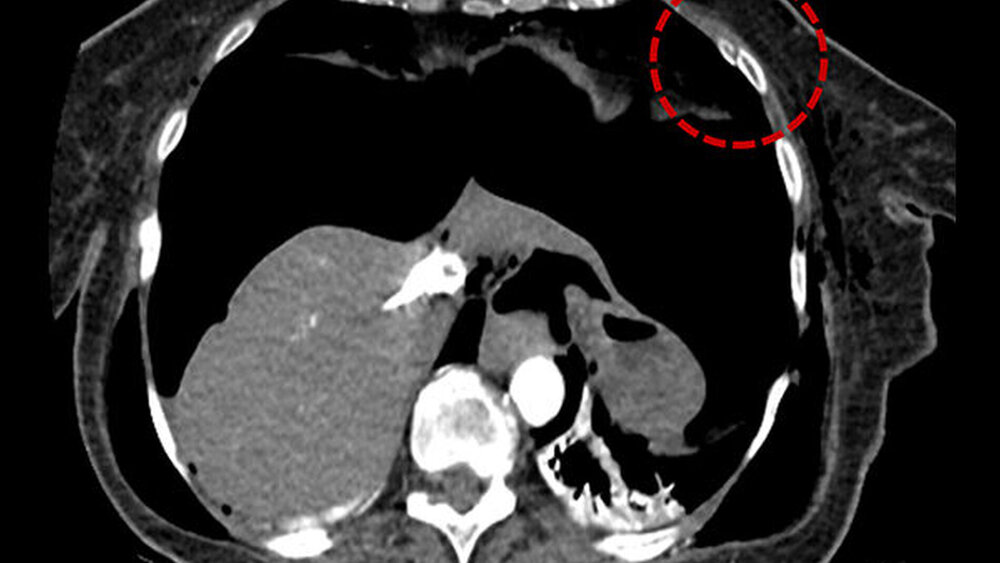

Im Rahmen der sofort eingeleiteten kardio-pulmonalen Reanimation erfolgte die unmittelbare Reintubation der Patientin, die einen schnellen ROSC (return of spontan circulation) zur Folge hatte. Im Zuge der durchgeführten Reanimationsmaßnahmen und der vorbestehenden Osteoporose kam es zu einer linksseitigen Rippenserienfraktur der Costae 3-7 (Abbildung 1), die einen beidseitigen Spannungspneumothorax und ein Pneumoperitoneum über eine Zwerchfellleckage nach sich führte.

Der Spannungspneumothorax wurde akut per Nadeldekompressionen und dann über Thoraxdrainagen beidseits entlastet. In der anschließend durchgeführten CT-Untersuchung von Thorax und Abdomen zeigte sich neben dem beidseitigen, entlasteten Mantelpneumothorax zusätzlich ein Pneumomediastinum mit Luftansammlungen im oberen, ventralen und dorsalen Mediastinum (Abbildung 2), zusätzlich dazu eine Ansammlung von freier Luft im Abdomen (Abbildung 3).